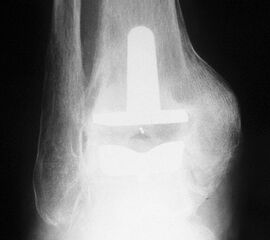

• Prothesenplanung anhand von Röntgenschablonen (Abb. 1 und 2).